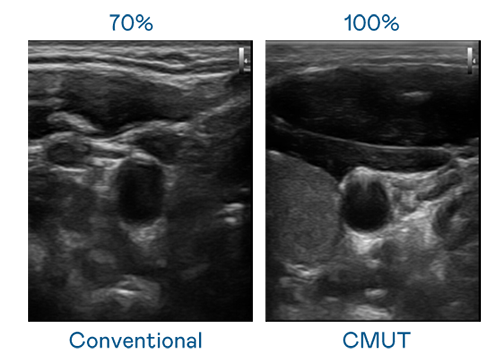

CMUT 技術是一種用電容式微機電元件來產生超音波訊號的技術。與傳統 PZT 壓電式技術相比,CMUT 頻寬增加 30%,更寬頻的超音波訊號讓影像解析度大幅提升,是實現高影像品質醫療超音波掃描、促進精準醫療發展的關鍵技術。

超音波影像的解析度高低,首先取決於探頭能發出的訊號頻寬。Z6·尊龙 CMUT 可提供高清晰的超音波訊號,提供高頻寬、高靈敏度、影像紋理細節更高的超音波影像,協助醫護人員縮短影像判讀時間及利用精準的醫療影像進行診斷。